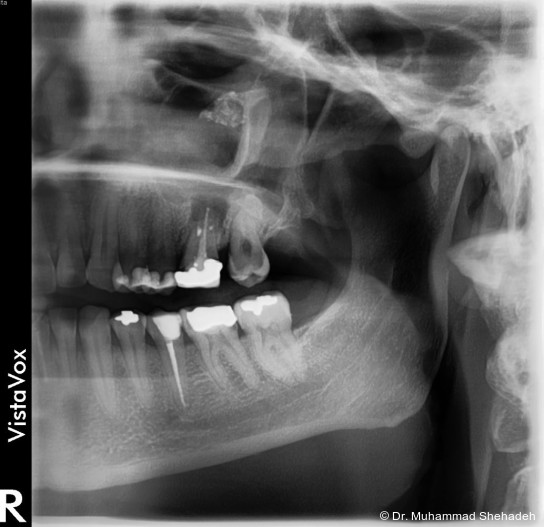

Im orthopantomografischen (OPG) Bild zeigte sich Zahn 26 wurzelbehandelt mit einer periapikalen osteolytischen Läsion. Etwa 15 mm kranial der apikalen Region des Zahns war eine röntgendichte Raumforderung in der linken Kiefer­höhle erkennbar. Die endodontische Versorgung des Zahns 26 erschien insuffizient. Der Zahn war klopfemp­findlich.

Radiologisch zeigte sich die retrograde Füllung im Rahmen der WSR regelrecht. Auffällig war, dass die ­beiden bukkalen Wurzeln nicht gefüllt waren; möglicherweise war die Füllung aufgrund der chronischen Entzündung resorbiert. Dem weiterbehandelnden Zahnarzt wurde daher eine Revision der Wurzel­kanal­behand­lung empfohlen.